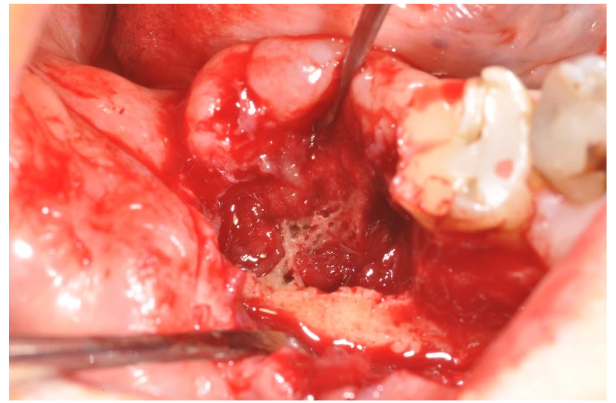

After the local anesthesia (with articain 4% with adrenaline 1:100.000, although the heart problems, but we needed a bleeding control) we opened a gingival flap removing the exophitic neoformation. The cortical bone was complete on the lingual side with a partial loss on the vestibular side: there was a big cavity that destroyed the alveolar edge behind the last residual molar (image 5). The cleaning of the upper part of the lesion made us to reach the deepest part of the bone lesion where it was possible to find granulation tissue with poor vessels and abundant necrotic bone. We completely removed these tissues with manual instrument and with ultrasonic instruments to have a total debridement of the cavity and to improve the bleeding from the residual bone walls (image 6). The necrotic bone surrounding the alveolar nerve was totally removed too.